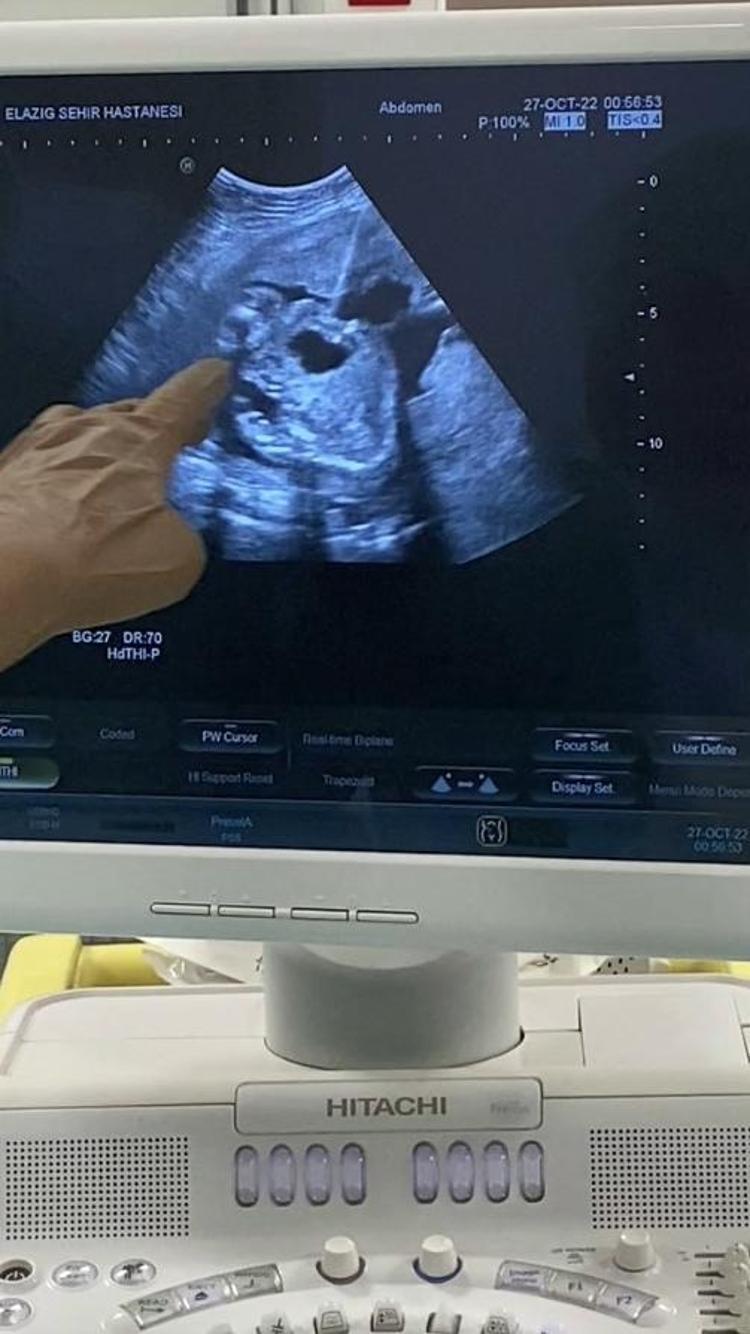

Anne karnında idrar çıkış yolunda darlık tespit edilen bebeğe stent takıldı

Yapılan operasyonla stent takılan bebeğin idrarını yapması sağlandı.

Uygulanan işlemin oldukça hassas olduğunu ifade eden Dr. Birsen Konukçu Palta, “Vesicoamniyotik Stent uygulaması ile bebeğin idrar kesesine takılan bir kanül ile idrarını yapması sağlanır.